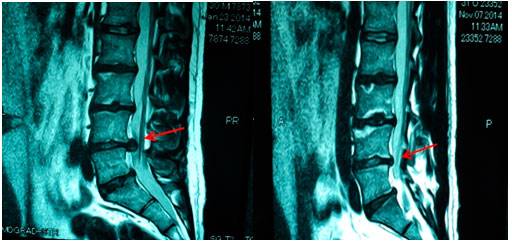

Хочется привести пример лечения пациента с большой грыжей:

Пациент 33 лет пришел на консультацию с жалобами на боли в пояснице. Боли постоянные. При осмотре есть симптомы незначительного натяжения корешка. На МРТ-снимках большая грыжа L4-L5. Все предыдущие консультации сводились к хирургическому лечению. Пациенту был назначен ортопедический режим, консервативное лечение и физиолечение. В течение года он наблюдался в ЦППиН, им было пройдено несколько этапов консервативного лечения. Пациент соблюдал все рекомендации. Через 10 месяцев был сделан контрольный снимок, на котором стало заметно, что грыжа «рассосалась».